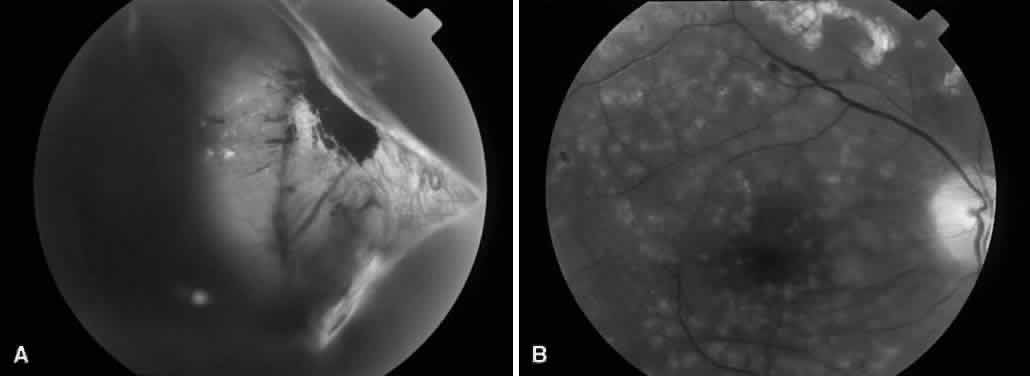

Segmentation was the earliest method used to release retinal traction caused by preretinal fibrovascular proliferation. A core vitrectomy is first performed (Fig. 1A). Anteroposterior traction then is released by circumferentially cutting the posterior vitreous surface around the area of epiretinal proliferation (see Fig. 1B). After the anteroposterior traction has been released and the formed vitreous has been removed, the posterior vitreous surface is cut between epicenters of fibrovascular adhesion, leaving islands of fibrovascular tissue. It also may be necessary to excise bridges of fibrovascular tissue connecting epicenters, using the vitrectomy probe or intraocular scissors (see Fig. 1C). Bleeding often is a problem during segmentation because the neovascular tissue is cut far away from its origin within the retina. Intraocular diathermy often is required to control bleeding from stumps of severed fibrovascular membranes. Raising the intraocular pressure also can be used temporarily to control intraoperative hemorrhage. Finally, panretinal endophotocoagulation is applied (see Fig. 1D).

Fig. 1. A. Core vitrectomy is performed. B. Peripheral vitreous is removed, releasing all anteroposterior traction on the epiretinal membrane. C. The epiretinal membrane is segmented by cutting bridging tissue between foci of fibrovascular adhesion. D. Segmentation has been completed, and panretinal endophotocoagulation is applied.